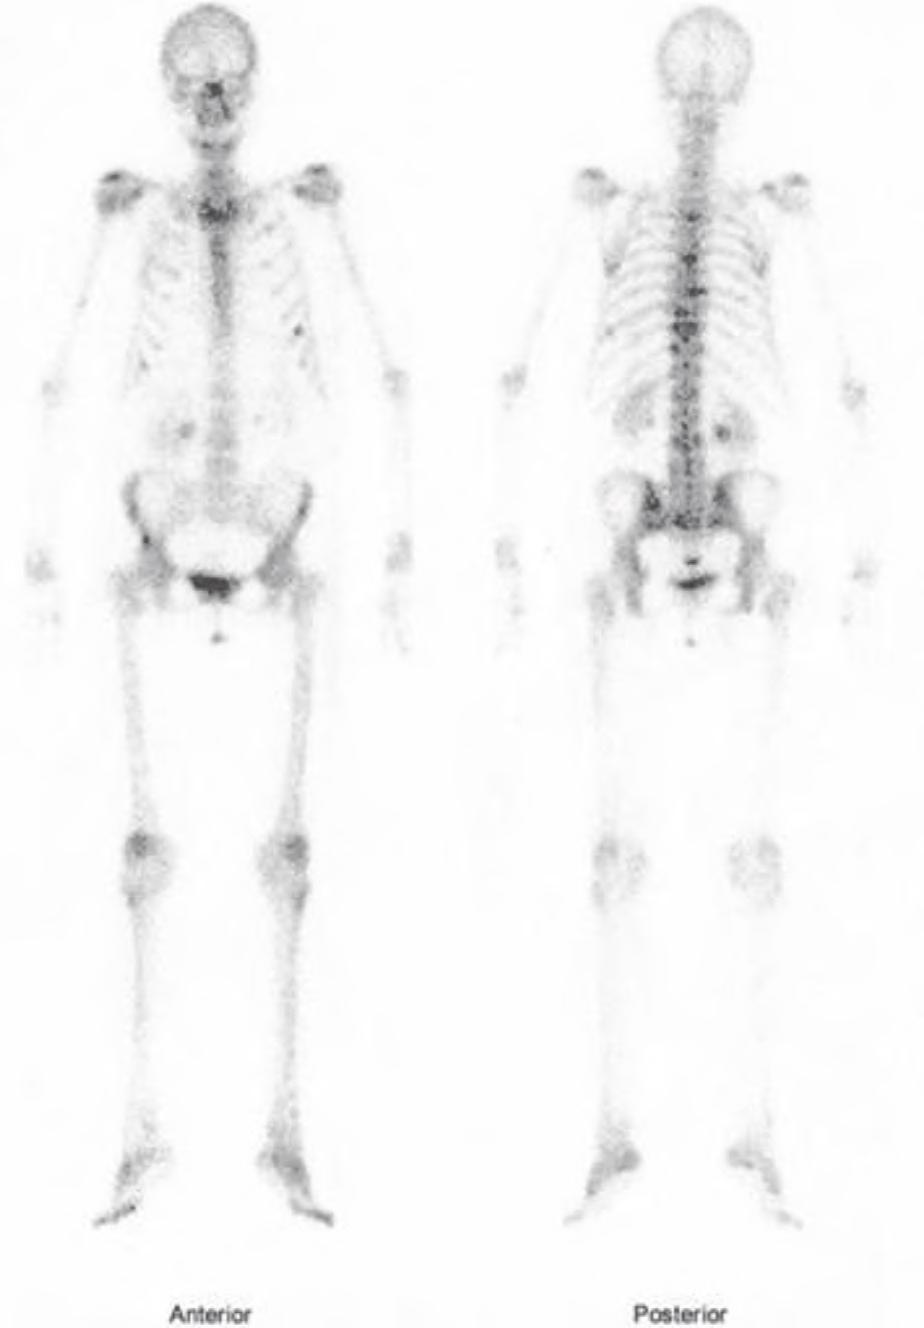

Scyntygrafia kości wykonywana jest z użyciem metylenodifosfonianu technetu (99mTc-MDP) (ryc. 2.44), aby ocenić pierwotne i wtórne zmiany w układzie kostnym, progresję choroby nowotworowej, np. w przypadku wzrostu markerów nowotworowych, oraz by ocenić wyniki leczenia.

Scyntygrafia kości – podejrzenie rozsiewu nowotworu do kości kręgosłupa i żeber.